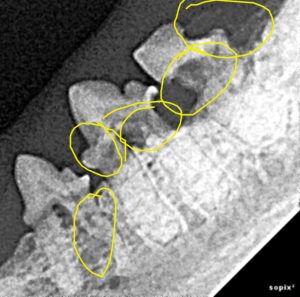

Figure 2. X-rays of the same teeth. The dark, moth-eaten areas on the teeth represent lost tooth structure due to resorption.

Late-stage lesions like the ones pictured above may be diagnosed during a thorough physical in a cooperative cat. However, early lesions are often at or below the gumline, making them impossible to recognize without x-rays – even though they may already be causing significant pain. Likewise, many cats will only allow the most cursory of oral exams without anesthesia – and cats with this disease are often particularly uncooperative for understandable reasons. In one study of 228 clinically healthy cats 29% were found to have at least one lesion on x-rays. This means regular anesthetized exams with x-rays are the only real way to know if your pet is affected or not.